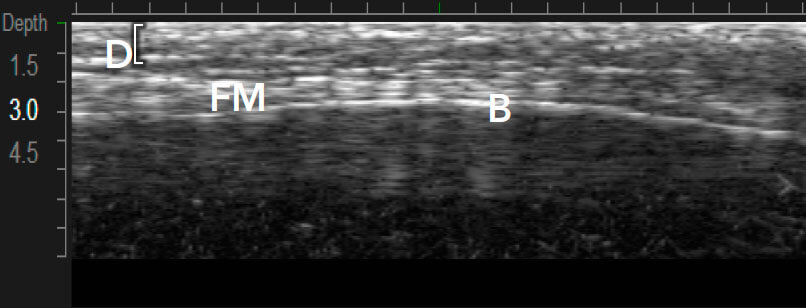

Ulthera - єдина технологія з візуалізацією в реальному часі

Приклади варіантів структури шкіри між індивідуальними пацієнтами 1,12

Візуалізація в реальному часі є основою Ultherapy®

Ultherapy® впливає на тканини за допомогою колімованого звукового зображення. Потім доставляє мікрофокусований ультразвук з точною глибиною і температурою, де лікування матиме найбільший вплив.1,3

MFU-V дає змогу лікарям точно бачити і враховувати всі анатомічні особливості в індивідуальному плані лікування, який буде ефективним.1